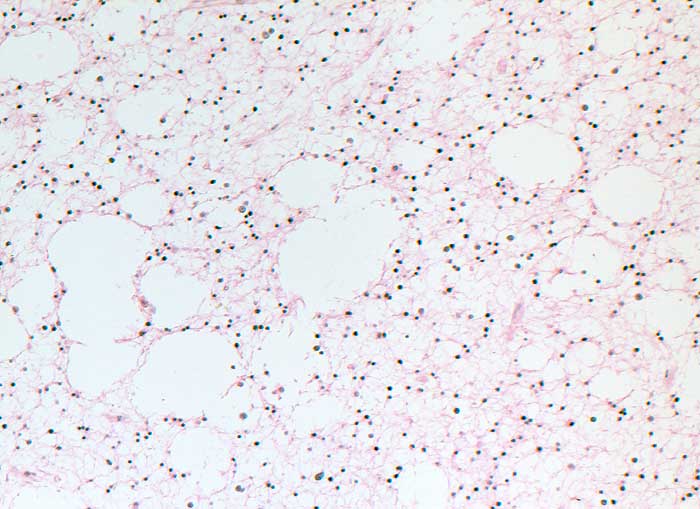

fibrilläres Astrozytom WHO II

Hirn parietal

Man erkennt einen mässig zellreichen fibrillären, stellenweise auch mikrozystischen Tumor. Keine Gefässproliferationen oder Nekrosen. Das Bild ist typisch für ein low grade Astrozytom.

Gliom rechts fronto-parietal.

Histologie

100